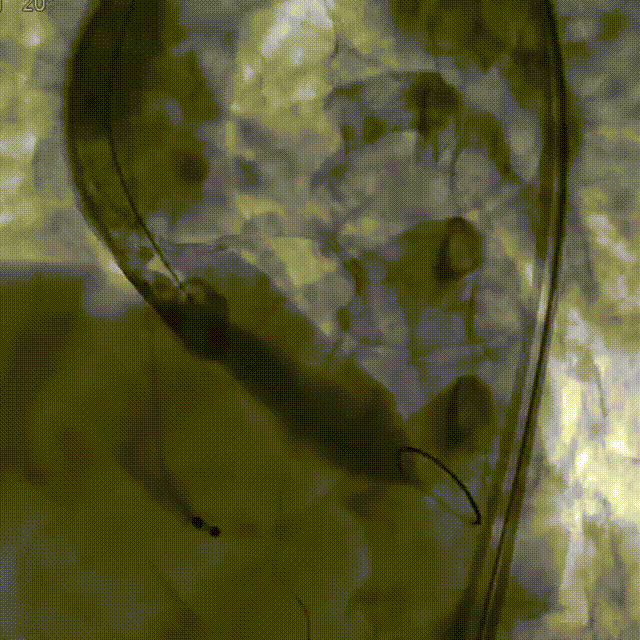

TaurusOne®释放过程:

瓣膜定位

瓣膜释放后形态位置良好,造影无返流

瓣膜展开后与术前策略讨论的风险预期相符,受无冠瓣较重钙化和瓣上结构整体的影响,瓣膜释放后的腰部形态受限,决定使用25mm球囊后扩治疗。

最终瓣膜形态和位置良好,造影无明显瓣周漏和返流。